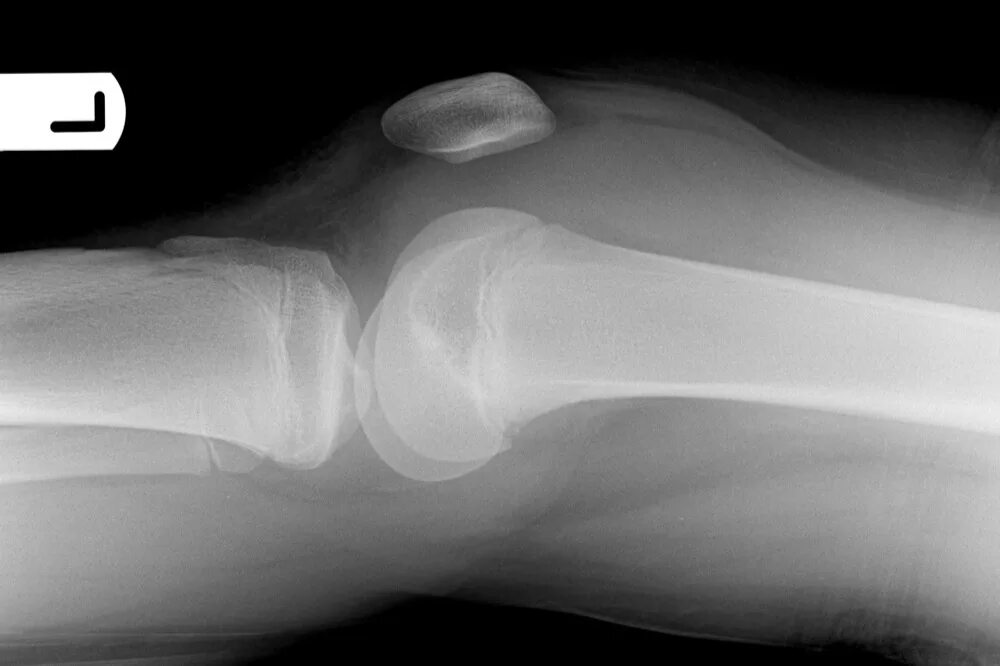

Болезнь осгут шляттера